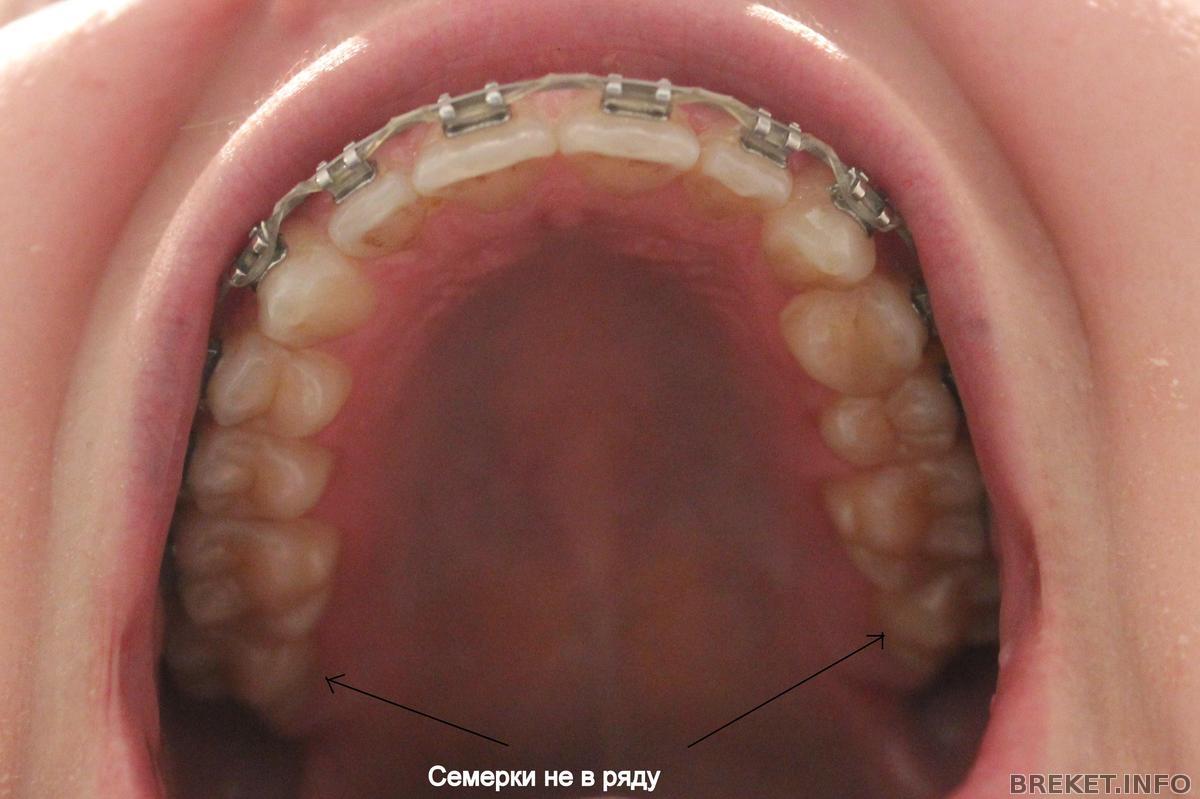

А дело вот в чем. Брекеты мне приклеили начиная от 6ок, т.е. 7 не подключены к системе. Так вот зубы у меня выравниваются, а 7 с ними даже в одном ряду не стоят, как я говорю "пляшут". Мне это очень не нравиться и я очередной раз поинтересовалась у орта, почему 7ки не в ряду с остальными зубами и как это исправлять. Она сказала, что чтобы исправлять это надо клеить брекеты начиная от 7. И мол сейчас это делать накладно, да и не нужно вовсе, потому цитирую "когда мы снимем брекеты, 7ки все равно встанут так как им удобно". Тогда вопрос - а нафига я ношу брекеты, если все потом встанет, как им удобно?!

По уму бы, конечно, семерки надо подключать. Но они совсем немного выходят из ряда, это не катастрофично.

Varechka, в идеале, как я себе представляла, что 6ки все-таки должны стоять ровно. Вот даже посмотреть на продемонстрированном коллаже от RaiseHopes. Там с семерками беда, но шестерки внизу хорошо стоят. А у меня вообще нет ровной "подковы". Про центр - конечно, если ровнять верх, то и низ, так как они в тандеме.